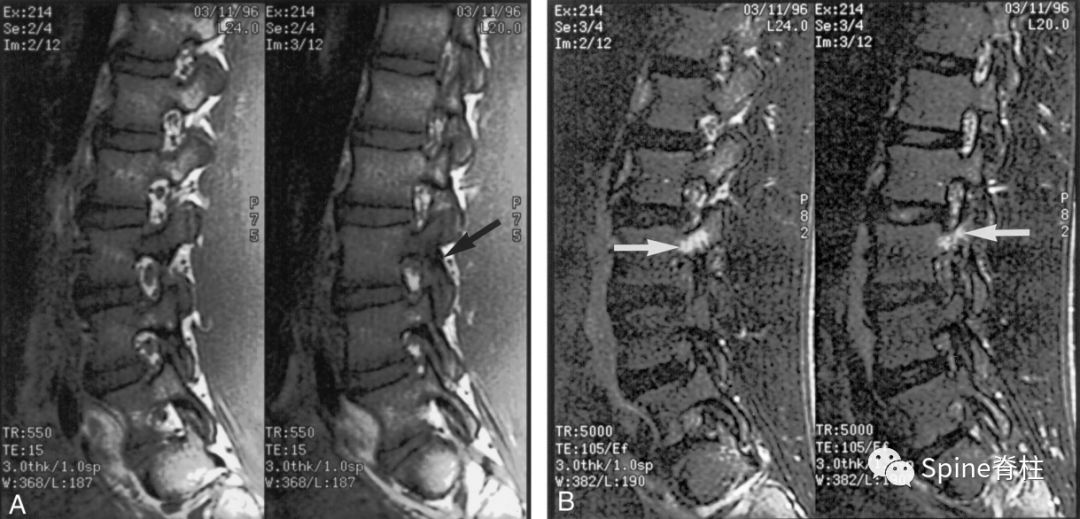

图:峡部完全断裂,断端存在明显间隙,且T2像明显水肿信号,提示L5左侧峡部裂(3级)

16岁的足球运动员,诉腰痛,以左侧为重。A:T1像可见腰5左侧峡部完全断裂(箭头);B:T2像,腰5左侧峡部、椎弓根和关节突水肿信号(箭头)

图:峡部完全断裂,但无T2水肿信号

提示为左侧L5峡部裂(4级)

13岁运动员,左侧腰骶部疼痛。A:T1像,左侧腰5峡部完全断裂(箭头);B:T2像,左侧腰5峡部清晰可见,骨质无信号改变,峡部缺损处可见轻微的高信号,提示可能为肉芽组织或积液